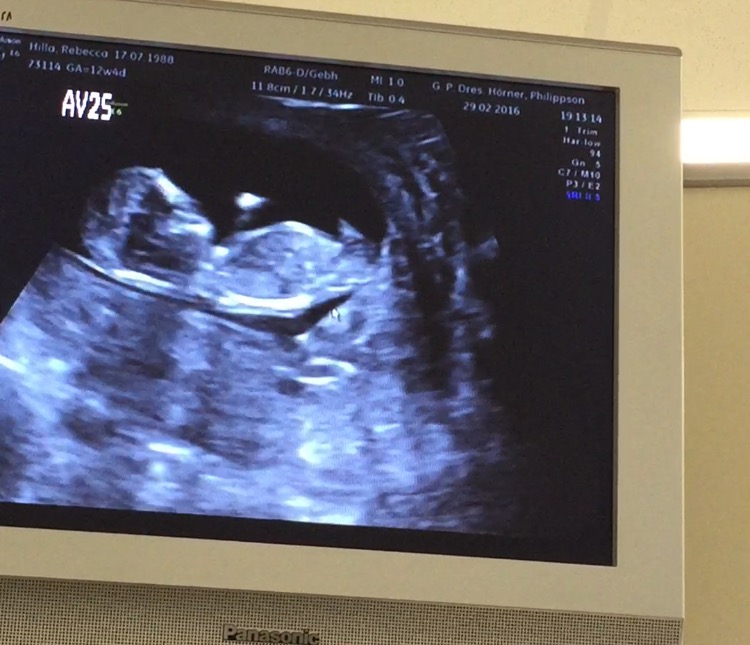

my doctor is leaning Boy because of something sticking out looking at the potty Shot, but said it was early... He did not know the Nub Theory, so I'm asking you Girls, is this a reliable picture? I have a video and am trying to cut some good Positions, but Baby is turning round all the Time...

Attachment 30177